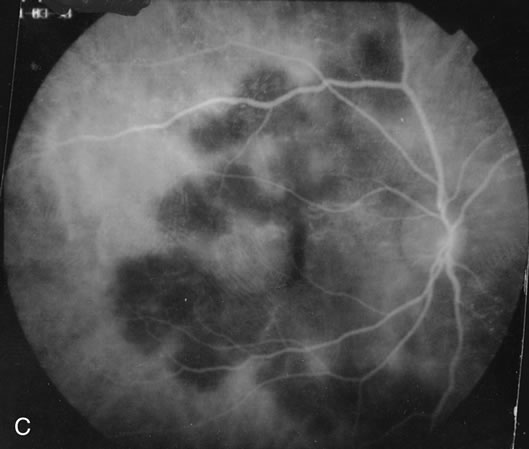

Some patients present with subretinal bands that extend between chorioretinal scars. In addition there may be initial active yellow choroidal lesions that subsequently become atrophic. Vitreous cells are usually present although they may be few and difficult to detect. Visual acuity loss in these cases may be due to active choroidal neovascularization, subretinal bands under the fovea, or from cystoid macular edema. The vast majority of affected patients are women with a mean age of 27 years and both eyes are usually involved. The affected individuals tend to be myopic.49 The age range is from 6 years to 76 years and there is no racial predilection.40 Whether it is a separate disease or a more severe form of multifocal choroiditis is controversial (Figs. 10 and 11). Aggressive therapy is warranted because it has a poorer prognosis than most cases of multifocal choroiditis. This syndrome has been called either diffuse subretinal fibrosis or progressive subretinal fibrosis syndrome.

Fig. 10. A. Fundus photograph showing the subretinal fibrosis extending from the disc to the periphery in a case of diffuse subretinal fibrosis. B. Fundus photograph showing the marked fibrosis in the midperiphery. C. Multifocal choroiditis type lesions noted in the inferior retina.

Fig. 11. A. Subretinal fibrosis in a case of multifocal choroiditis. B. Fellow eye showing classic coalescent hyperpigmented chorioretinal scars of multifocal choroiditis. These scars also can be seen in presumed histoplasmosis syndrome, but the subretinal fibrosis is extremely rare in presumed ocular histoplasmosis syndrome (POHS).